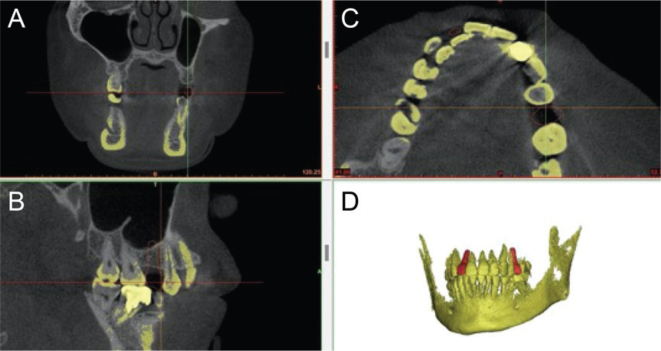

Purpose: To investigate the correlation between the marginal bone height of implants in the posterior maxilla of patients with periodontal disease and the inclination of cusp, providing a theoretical basis for the occlusal design of implant restorations in such patients.  Methods: A total of 80 patients with periodontal disease who underwent implant restoration in the posterior maxilla (55 men and 25 women; mean age 56.66 ± 12.70 years) were selected, with a total of 80 implant restorations (one implant restoration per patient). In addition to recording the main research factor of the inclination of cusp, general patient information, implant characteristics and restoration characteristics were taken, and retrospective analysis of the case data and imaging data of the 80 patients from over 3 years was conducted. Cone beam computed tomography was performed preoperatively and 3 years after implant loading to measure and calculate the marginal bone height of the implants using the One Volume Viewer software. Correlation analysis was performed to determine the relationship between the inclination of the cusp and marginal bone height.  Results: There was a positive correlation between the inclination of cusp and the marginal bone height of the implants, with a correlation coefficient of 0.661 (p < 0.001); the diameter of the implants, implant type and restoration type were negatively correlated with the marginal bone height of the implants, with correlation coefficients of -0.364 (p = 0.001), -0.232 (p = 0.038) and -0.298 (p = 0.007), respectively.  Conclusion: When designing the occlusion of implant restorations in the posterior maxilla of patients with periodontal disease, it is advisable to appropriately reduce the restoration's inclination of cusp.